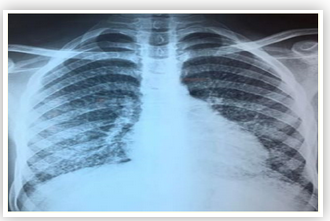

Tuberculosis Revealing Niemann Pick Disease Type B in a Teenager

Amal Ouayad, Karima Elfakiri, Noureddine Rada, Ghizlane Draiss, Naima Fdil and Mohammed Bouskraoui.